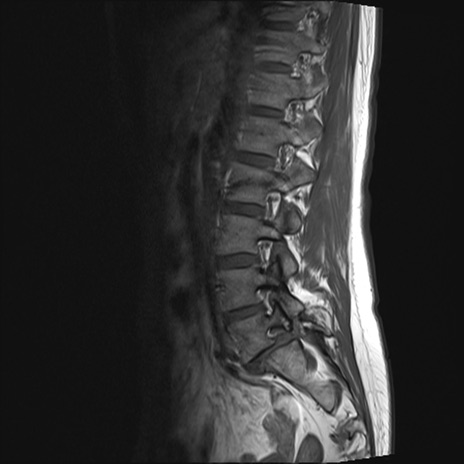

【整形】TIPS症例4 腰椎MRI T1WI(矢状断像)

腰椎MRI

T2WI(矢状断像)